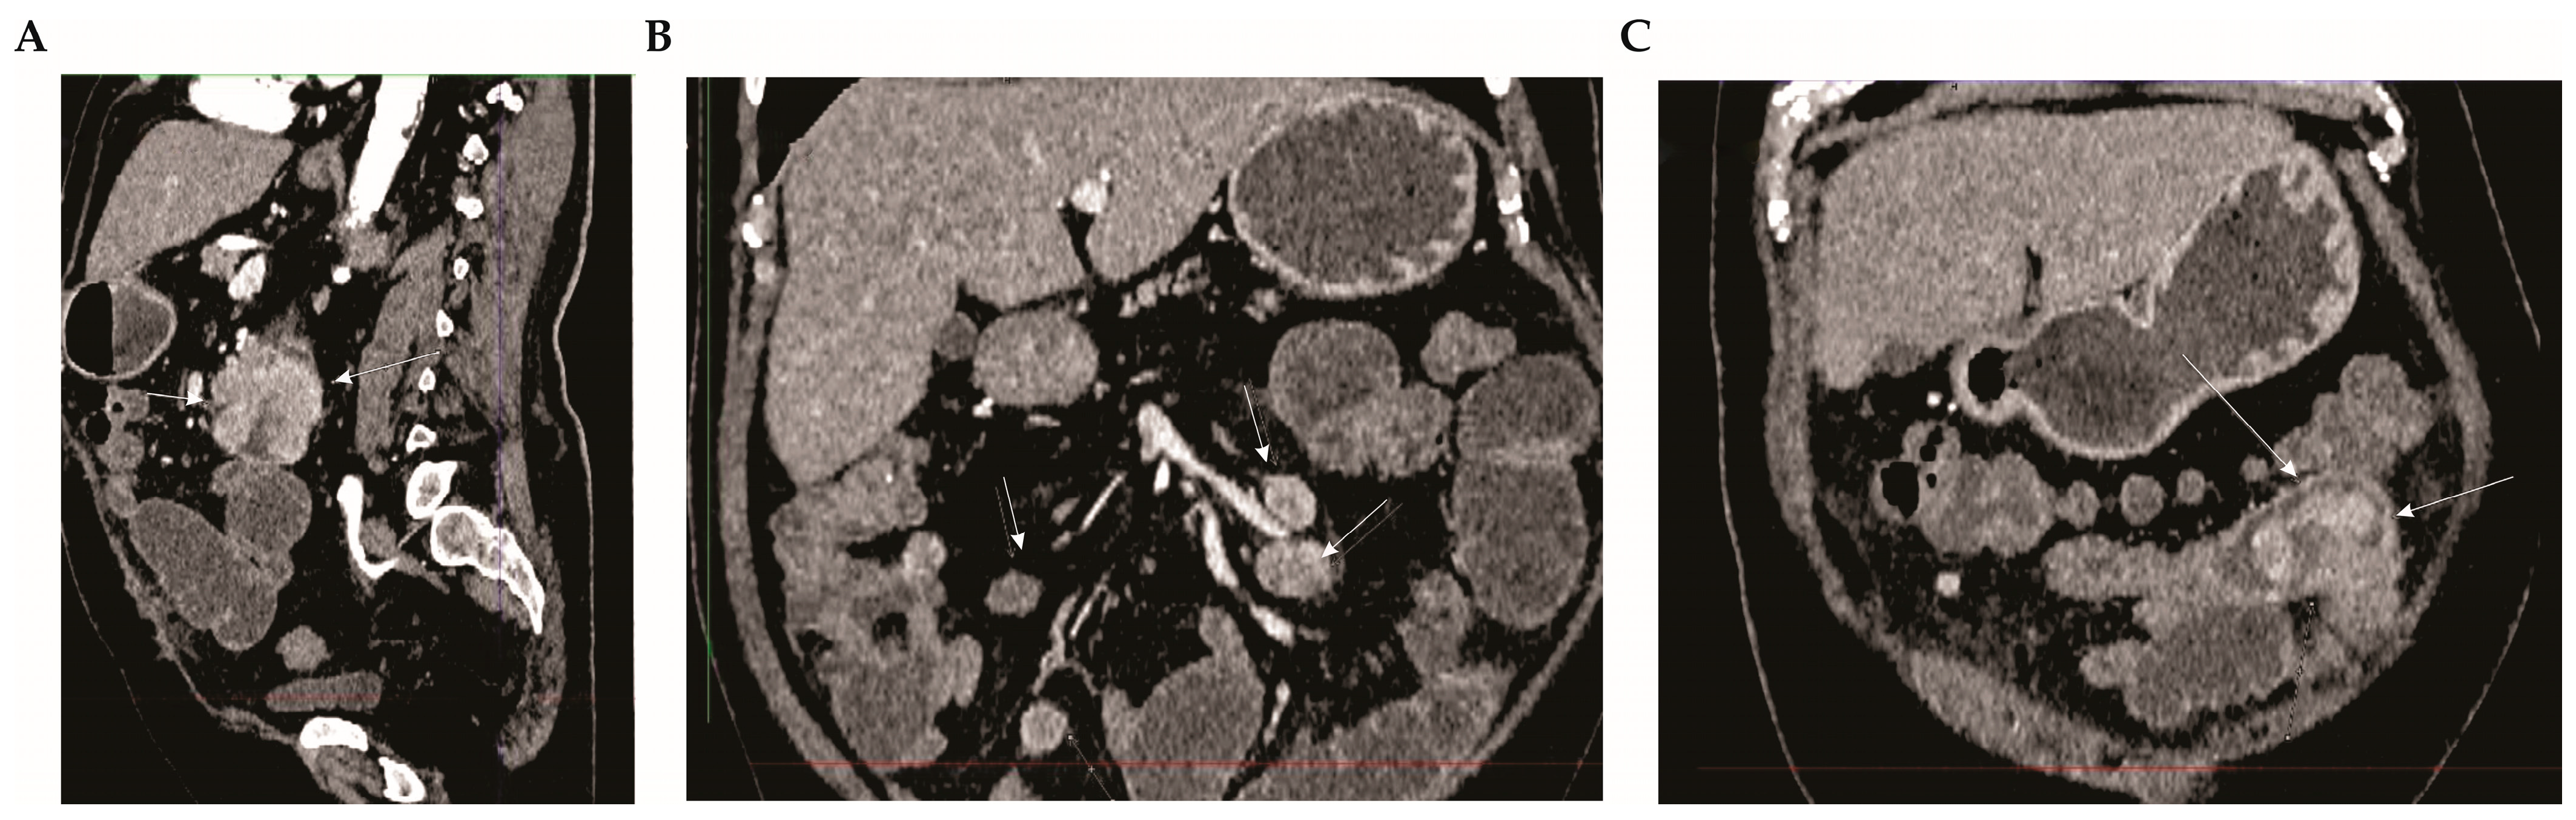

2.2. Diagnostic Assessment

2.3. Therapeutic Intervention